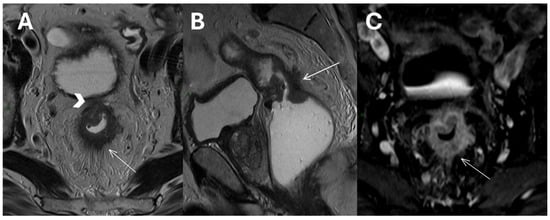

- Lymph node involvement and surgical risk: Notably, our study identifies lymph node involvement as a predictive factor for postoperative bleeding. Lymph node involvement is a crucial prognostic factor in rectal cancer, making preoperative neoadjuvant therapy recommended for these patients to help lower the risk of local recurrence [11,43]. Although MRI is the gold standard for staging, it is less accurate for N staging compared to T staging, with sensitivity and specificity ranging from 58 to 77% and 62 to 74%, respectively [44,45,46]. Other imaging methods, such as computed tomography, have demonstrated similar diagnostic accuracy [47]. Our data suggest that the presence of nodal disease, which indicates a more invasive tumor, may require more delicate and extensive surgical interventions, potentially increasing the risk of bleeding. This insight should encourage surgeons to consider preoperative strategies to minimize this risk, such as advanced surgical techniques or preoperative interventions (Figure 3).